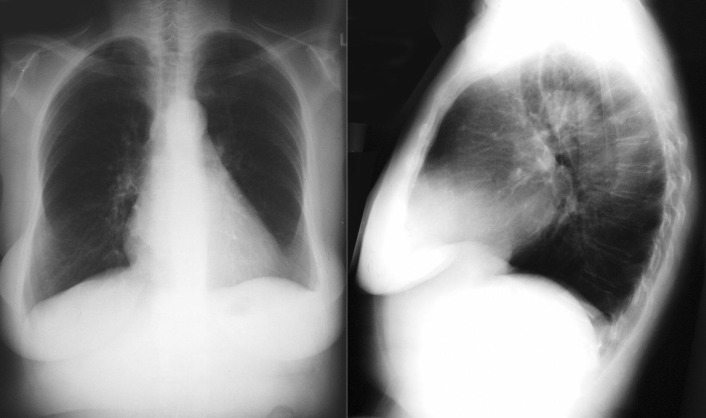

The radiographic findings of mitral stenosis ( Graphic 15-1 ; Figs. 15-1 to 15-16 ) reflect the pressure overload of the left atrium and pulmonary veins, and later of the right heart. As well, the commonly associated chronic atrial fibrillation contributes to (bi)atrial dilation. Associated rheumatic valvular lesions such as mitral regurgitation, tricuspid regurgitation, aortic insufficiency, and aortic stenosis/aortic insufficiency are common, and they alter the appearance of the heart.